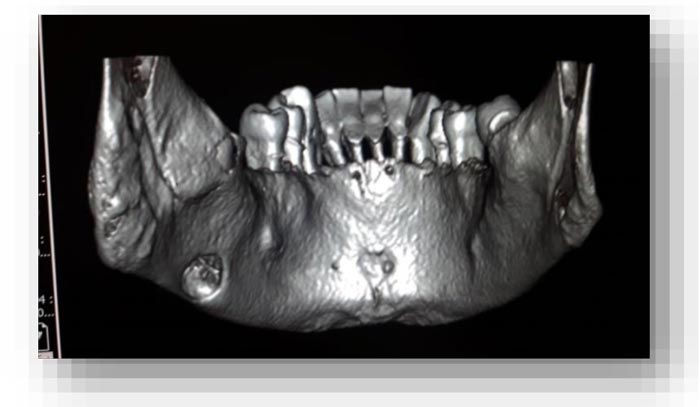

From the objective exam and the panoramic radiography, we observed the presence of multiple edentulous areas which needed to be rehabilitated. As part of an implant-prosthetic plan of care, Spiral Computerized Tomography was prescribed to him (Fig. 3), obtaining bi-dimensional reconstructions as panorex, parasagittal slices by multiplanar reformation and tridimensional reconstructions by volume rendering [12, 13].

The bi-dimensional reconstructions in parasagittal slices also permitted better identification of the closeness of the bone cavity to the canal of the alveolar inferior omolateral nerve, whereas the computerized volume rendering offered a more accurate view of the surrounding anatomical features (Figs. 6-12).